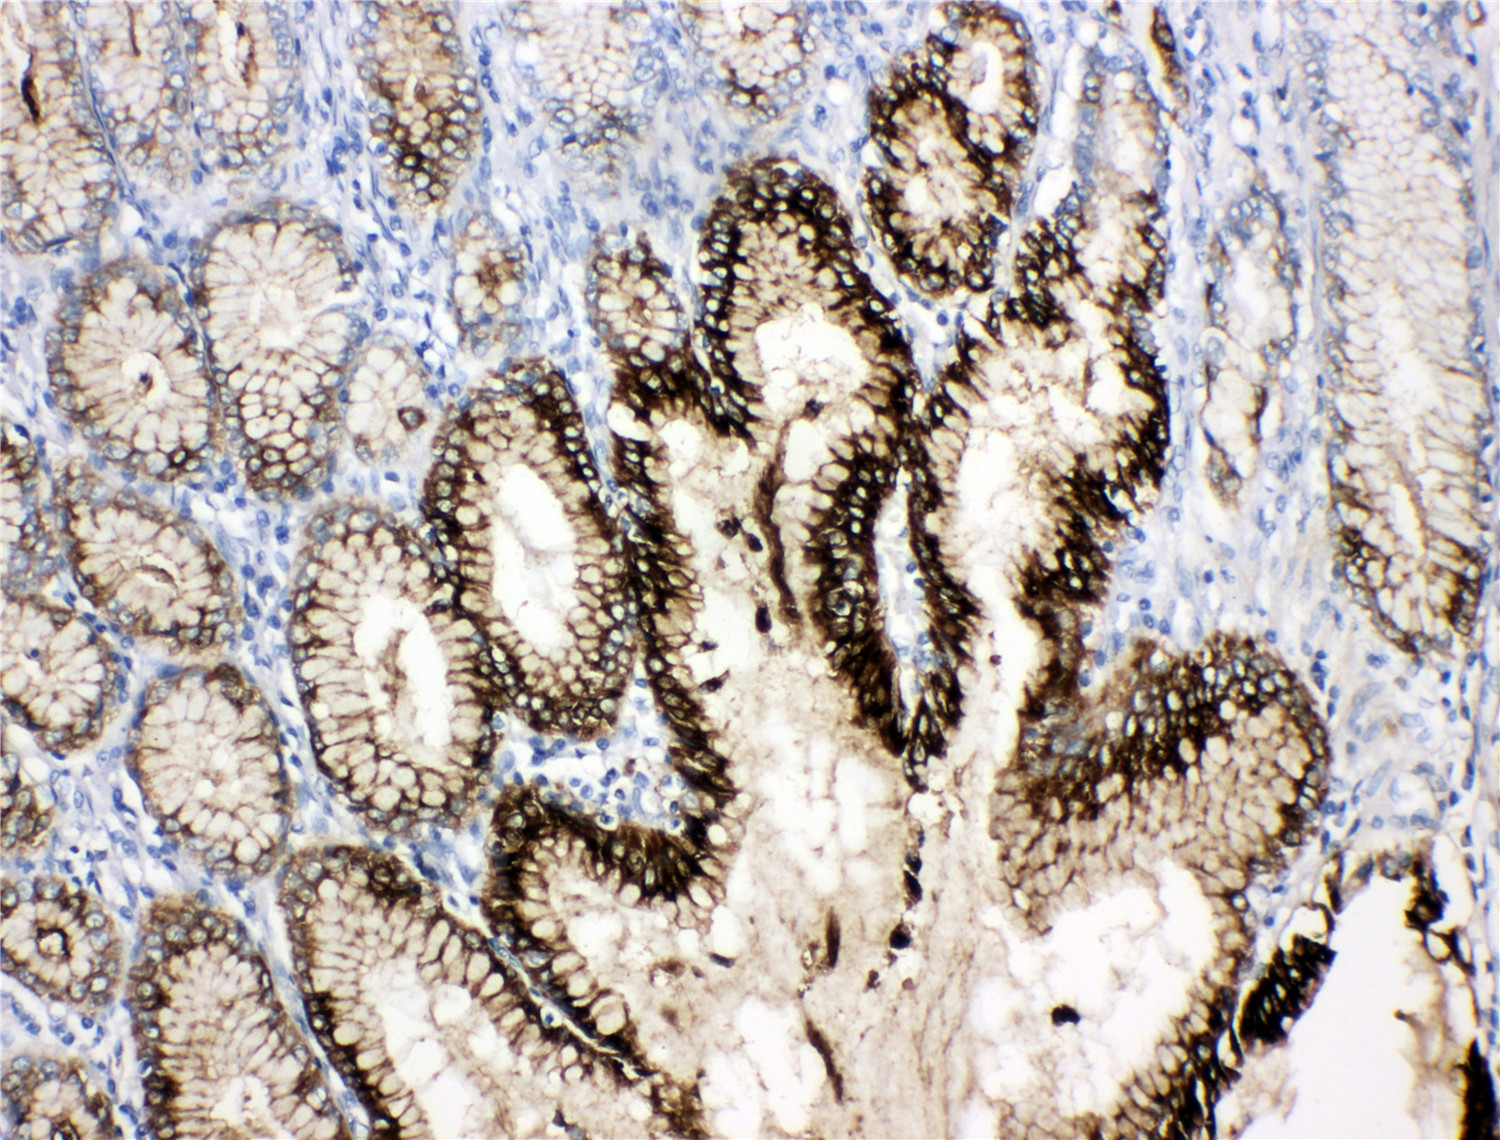

IHC analysis of Trefoil Factor 1/TFF1 using anti-Trefoil Factor 1/TFF1 antibody (BA4597-1) .

Trefoil Factor 1/TFF1 was detected in a paraffin-embedded section of human gastric cancer tissue. The tissue section was incubated with rabbit anti-Trefoil Factor 1/TFF1 Antibody (BA4597-1) at a dilution of 1:200 and developed using HRP Conjugated Rabbit IgG Super Vision Assay Kit (Catalog # SV0002) with DAB (Catalog # AR1027) as the chromogen.